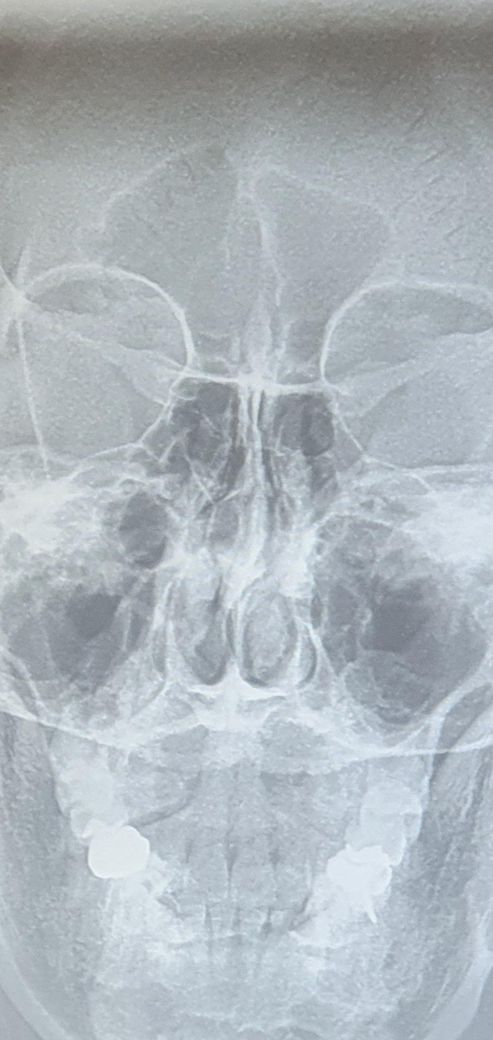

저 비중격만곡증 심한지 봐주실 수 있을까요?

치과에서 x-ray? 뭘 찍었는데

코가 너무 휜 거 같아서요.

한쪽 코만 답답하기도 해서

그리고 비중격만곡증 수술하는 게 좋을 지 의견도 궁금합니다.

• 1번 째 사진

• 안녕하세요. 이송재 이비인후과 전문의입니다.

보통은 ct로 연속된 사진을 보고 만곡 정도를 평가하게 됩니다. 가까운 이비인후과 내원하여 진료 받아보시고, 평소에도 코 답답한 증상이 있으면 수술도 고려해 보시기 바랍니다.